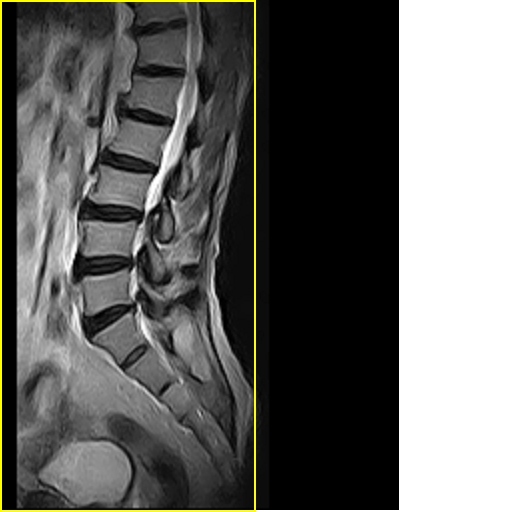

标题: MRI0859:[原创]腰椎,男,78岁,右下肢跛行两月 [打印本页]

男,78岁,右下肢跛行两月.

腰间盘膨出、黄韧带肥厚、可疑先天性腰椎管狭窄。

退行性骨关节病:增生、椎间盘变性、膨出...

退行性病变:增生、椎间盘变性、膨出[l4-5、l5-s1 椎间盘膨出]

退行性骨关节病:增生、椎间盘变性、膨出..黄韧带肥厚.